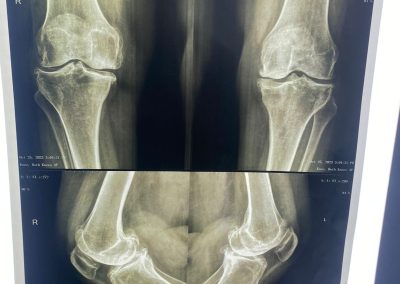

السيده/ عزه الرخاوي العمر ٦٨ عام كانت تعاني من تآكل شديد بالركبتين تم تغيير المفصل الايسر منذ ٣ أعوام تم تغيير المفصل الايمن منذ ٨ اشهر هي الآن تمشي بشكل طبيعي تماما